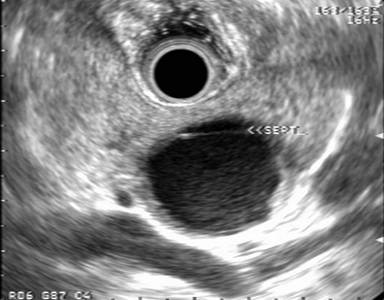

The EUS appearance of mucinous cystic neoplasm is variable. They are commonly associated with a visible wall and septations of variable thickness, and peripheral calcifications can be seen in some cases (Figures 1 and 2) [43]. Invasive malignancy has been associated with the presence of thick or irregular cyst wall, intramural nodules or solid components and larger cyst size (Figure 3) [14]. EUS-FNA cytology could reveal columnar epithelial cells in up to half of the patients in association with extracellular mucin [34, 46]. Mucin is frequently identified on EUS-FNA of mucinous cystic neoplasm and cyst fluid is typically clear with elevated CEA levels and low amylase. Mucinous cystic neoplasms are premalignant lesions but the risk of malignant degeneration is likely less than that of IPMN [45]. The risk of malignancy in these tumors described in a series of 163 patients was found to be 17.5% [47]. Therefore, surgical resection is recommended for all surgically fit patients. The prognosis after surgery for mucinous cystic neoplasm that have not undergone malignant transformation is excellent and the 5-year survival for mucinous cystadenocarcinomas post resection exceeds 60% [6, 48].

Figure 3. EUS findings in a middle age female patient with a mucinous cystic neoplasm in the body of the pancreas. A thick wall and a solid mass are features suggestive of malignancy. Surgical resection confirmed mucinous cystadenocarcinomas. |